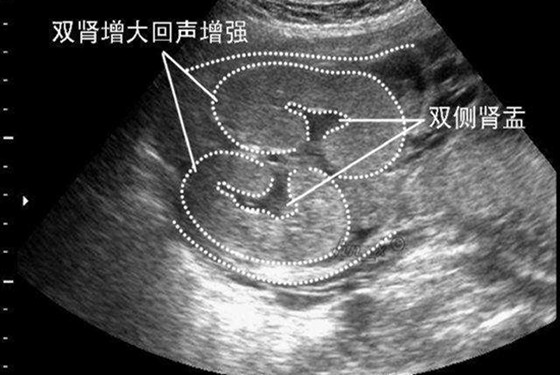

这么说吧,我们都知道人体有两个肾脏,两条输尿管,而孕麻麻在做B超时,会检查出胎儿的发育状态,有的显示胎儿双肾未见分离,有的会显示胎儿双肾分离的状态。正常健康的状态下胎儿双肾是没有分离的,这表明胎儿的肾与输尿管连接处发育正常;而造成双肾分离的原因,如胎儿憋尿的情况,还有就是肾结石、输尿管畸形所导致的肾盂被充盈变大的情况。